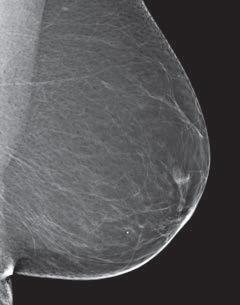

The breasts contain fatty, glandular, and fibrous connective tissues.

- Fatty (Adipose) tissue largely determines your breast size. It fills in the spaces between the glandular, and fibrous connective tissue

- Fibrous connective tissue supports, and holds your tissues, and muscles in place.. Both glandular, and fibrous connective tissue appear white on a mammogram.

Dense breast tissue, as seen on a mammogram, has more fibrous connective tissue and glandular tissue, and less fatty tissue. It is often inherited, but menopausal hormone therapy, and low body mass index are factors associated with breast density. Dense breast tissue is a risk factor for breast cancer, and a radiologist can tell if a woman has dense breasts.

A mammogram uses X-rays (ionizing radiation) to create images of the inside of the breast to check for cancer and other conditions. It can be used for screening to detect cancer, for instance, before there’s a lump in the breast, or to assist in the diagnosis of cancer. Radiologists use mammograms to interpret, and classify breast density into four categories.